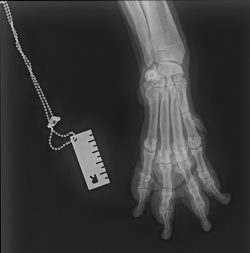

Perro macho castrado de 12 años que desde hace más de 6 meses se muerde y se lame la zona metacarpofalángica de la extremidad torácica derecha. A veces cojea de forma intermitente durante el paseo. En consulta, el examen físico es compatible con la normalidad. En la exploración ortopédica se observa crepitación a la exploración de las falanges. Realizamos una radiografía anteroposterior de las falanges de la extremidad torácica derecha (Figura 2).

Pregunta: ¿Cuál sería tu principal diagnóstico diferencial?

La radiografía muestra cambios crónicos en varias falanges, con remodelación ósea, proliferación y cierto aumento de tejidos blandos. Estos hallazgos pueden observarse en procesos prolongados que cursan con dolor e inflamación. El diagnóstico diferencial inicial incluía neoplasia digital, osteomielitis o artritis erosiva, dado el aspecto irregular del hueso. Sin embargo, en este paciente debido a la presentación clínica y la distribución de las lesiones, finalmente se diagnosticó artrosis avanzada de las articulaciones interfalángicas, causa habitual de lamido persistente, molestia y cojera intermitente en perros mayores.